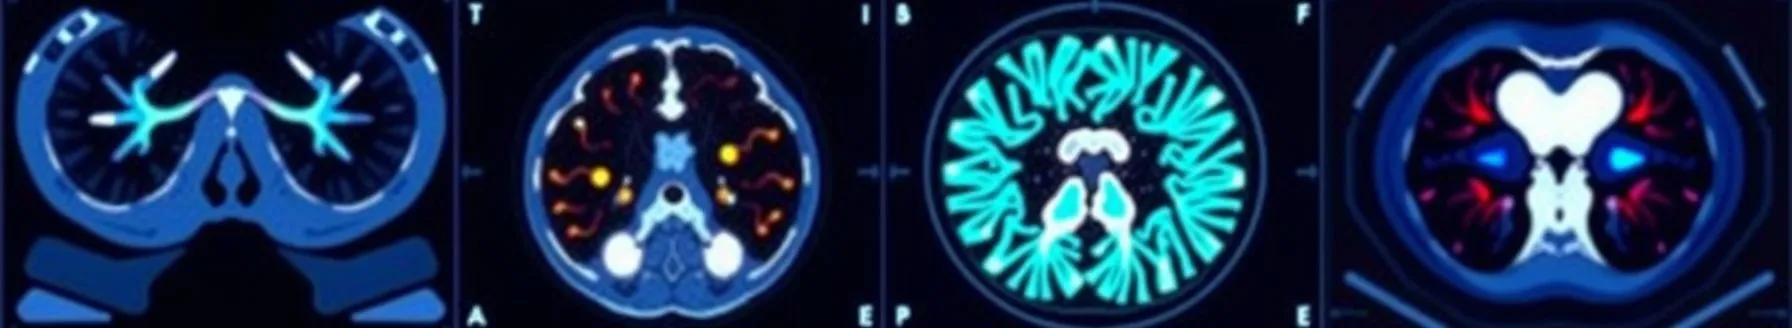

PET and CT scans are medical imaging techniques that are used to diagnose and monitor a wide range of medical conditions. PET scans use a radioactive tracer that is injected into the patient's bloodstream. This tracer accumulates in the body's tissues, and the PET scanner detects the emitted...

- PET CT is a fusion of biological (PET) and anatomical (CT) imaging, offering a more comprehensive view compared to individual scans. CT provides morphological information, while PET focuses on metabolic activity. This combination yields better results in diagnosing and managing head and neck cancers.